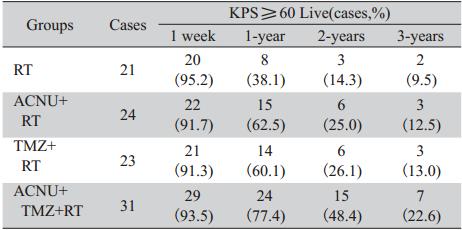

各组患者术后均定期复查头颅CT或MRI及血 常规,以了解患者手术后恢复及肿瘤复发情况, 术后定期行Karnofsky评分以评价患者术后的生存 质量。每周进行一次血常规检查,每隔4周检查 肝、肾功能及常规体检,以评价药物毒性和患者 耐受性,进行临床评价,以便调整用药,直至给 药结束为止。每4~6周复查头颅CT或者MRI检查 以判定肿瘤生长情况见图1~图3。不良反应以主观 症状和客观体征评价为主,按WHO标准分为0~Ⅳ 度。

A,B:enhanced MRI simulation before operation. There was a large cystic lesion with obvious enhancement of the cystic margin in the right parietal lobe.C,D:enhanced MRI simulation 3 years after operation. There was no obvious enhancement in the right parietal lobe 图2 42岁女性间变性星形细胞瘤(WHO Ⅲ级)患者手术前后增强MRI对比Figure 2 42Comparison of enhanced MRI simulation of a 42 years old female with anaplastic astrocytoma(WHO grade Ⅲ)before and after operation |